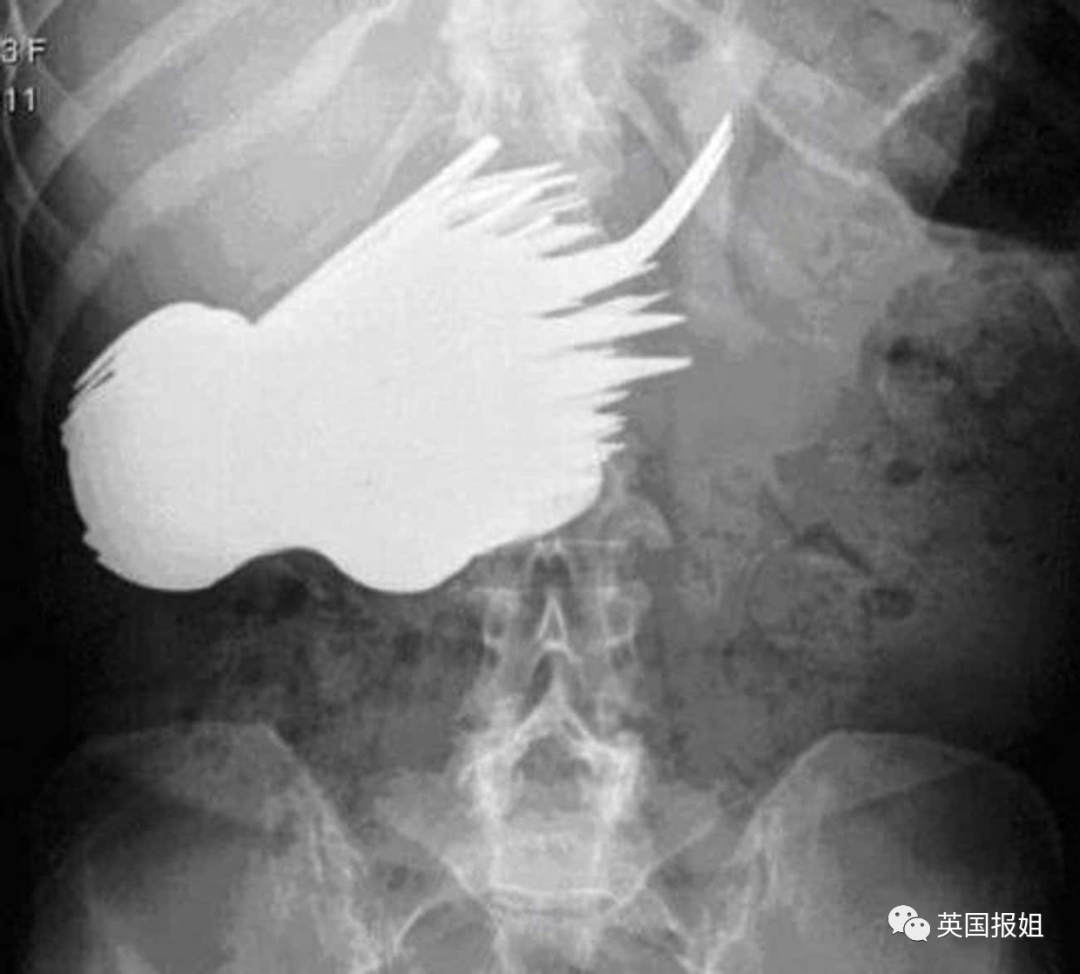

一名军迷男子下体塞入了一枚17cmX6cm的二战时期反坦克炮弹,当然,他说是滑倒造成的。

医生非常慌,就算她医术再高明,也是没有进行过军械拆卸的,于是她职业生涯中第一次报警叫来了拆弹部队。

经过了拆弹部队和医院多个诊室的会诊,终于判定炮弹已没有引爆危险,在复杂的手术后将其取出。